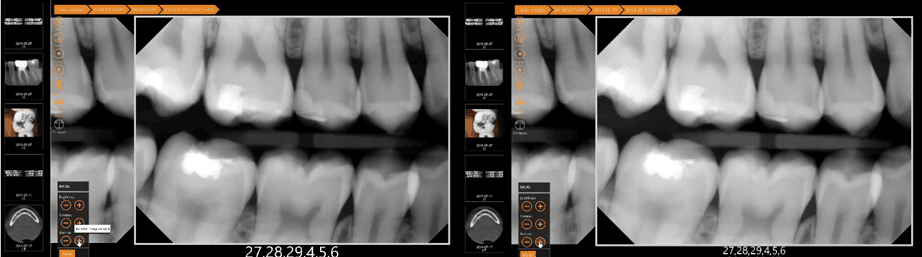

We’ve now learned that you can adjust contrast in an X-ray for greater or lesser detail at the ends of the black and white spectrum, but what should you do if you want to adjust just the grays? Here’s where gamma correction can help.

By adjusting the gamma, you can alter all the varying grays to increase detail in the middle range of shades in a radiograph.

Below, you can see how adjusting the gamma creates more detail in the gray areas of the radiograph.